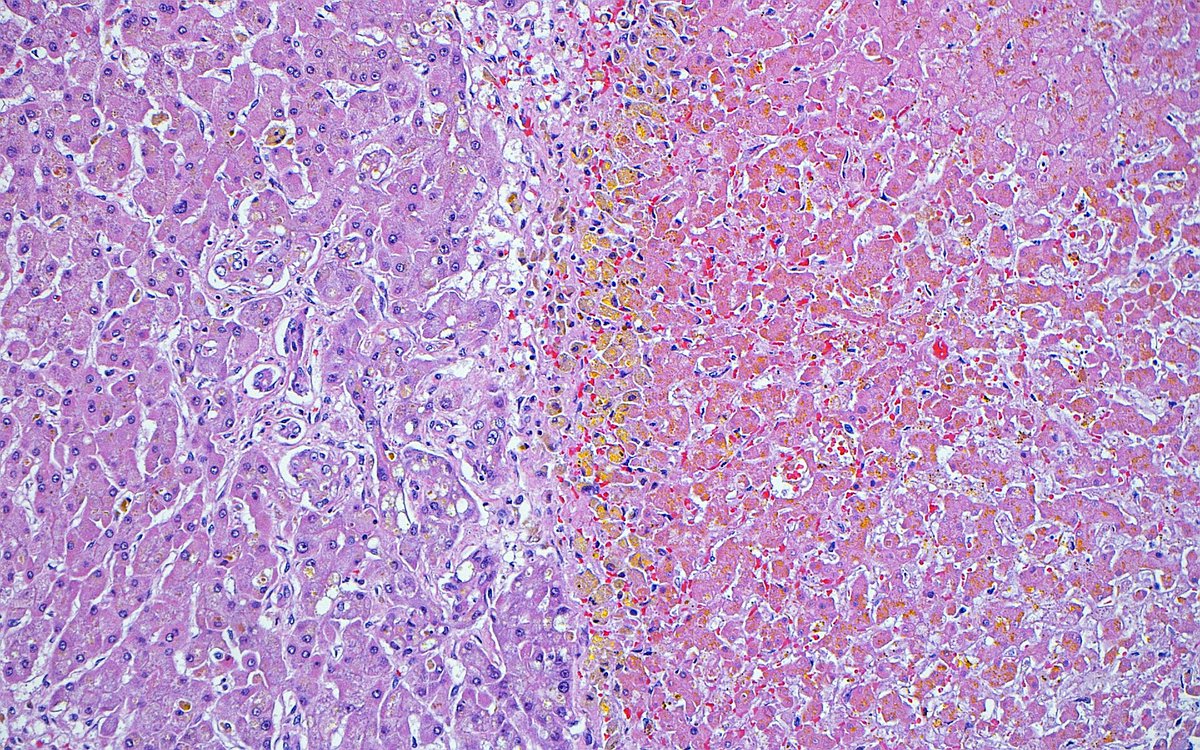

"Edge of destruction" ~ Interface between necrotic (right) and viable (left) liver in a patient treated for hepatocellular carcinoma. #pathology #pathart #liver #liverpathology #hepatology #oncology